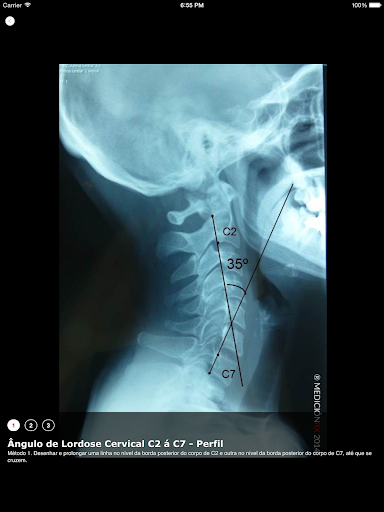

é o app no qual você encontrará a descrição e o traçado das técnicas de medição radiológicas em ortopedia e traumatologia. 120 imagens radiográficas de alta qualidade. Dirigida a fisioterapeutas especialistas nas áreas de terapia manual (RPG, osteopatia, etc.), etc. Você poderá realizar sua busca, digitando "regiões", "patologias" ou "medições". Você também poderá realizar sua busca inserindo a palavra-chave na lupa de busca. Não é o objetivo deste app, substituir avaliação clínica que fazemos aos nossos pacientes. Este app tem como objetivo explorar os métodos de medição em estudos radiológicos complementários, e demonstrar e quantificar as alteracoes radiológicas obtidas após os tratamentos kinésicos. Esta aplicação está disponível em Português, Espanhol e Inglês.